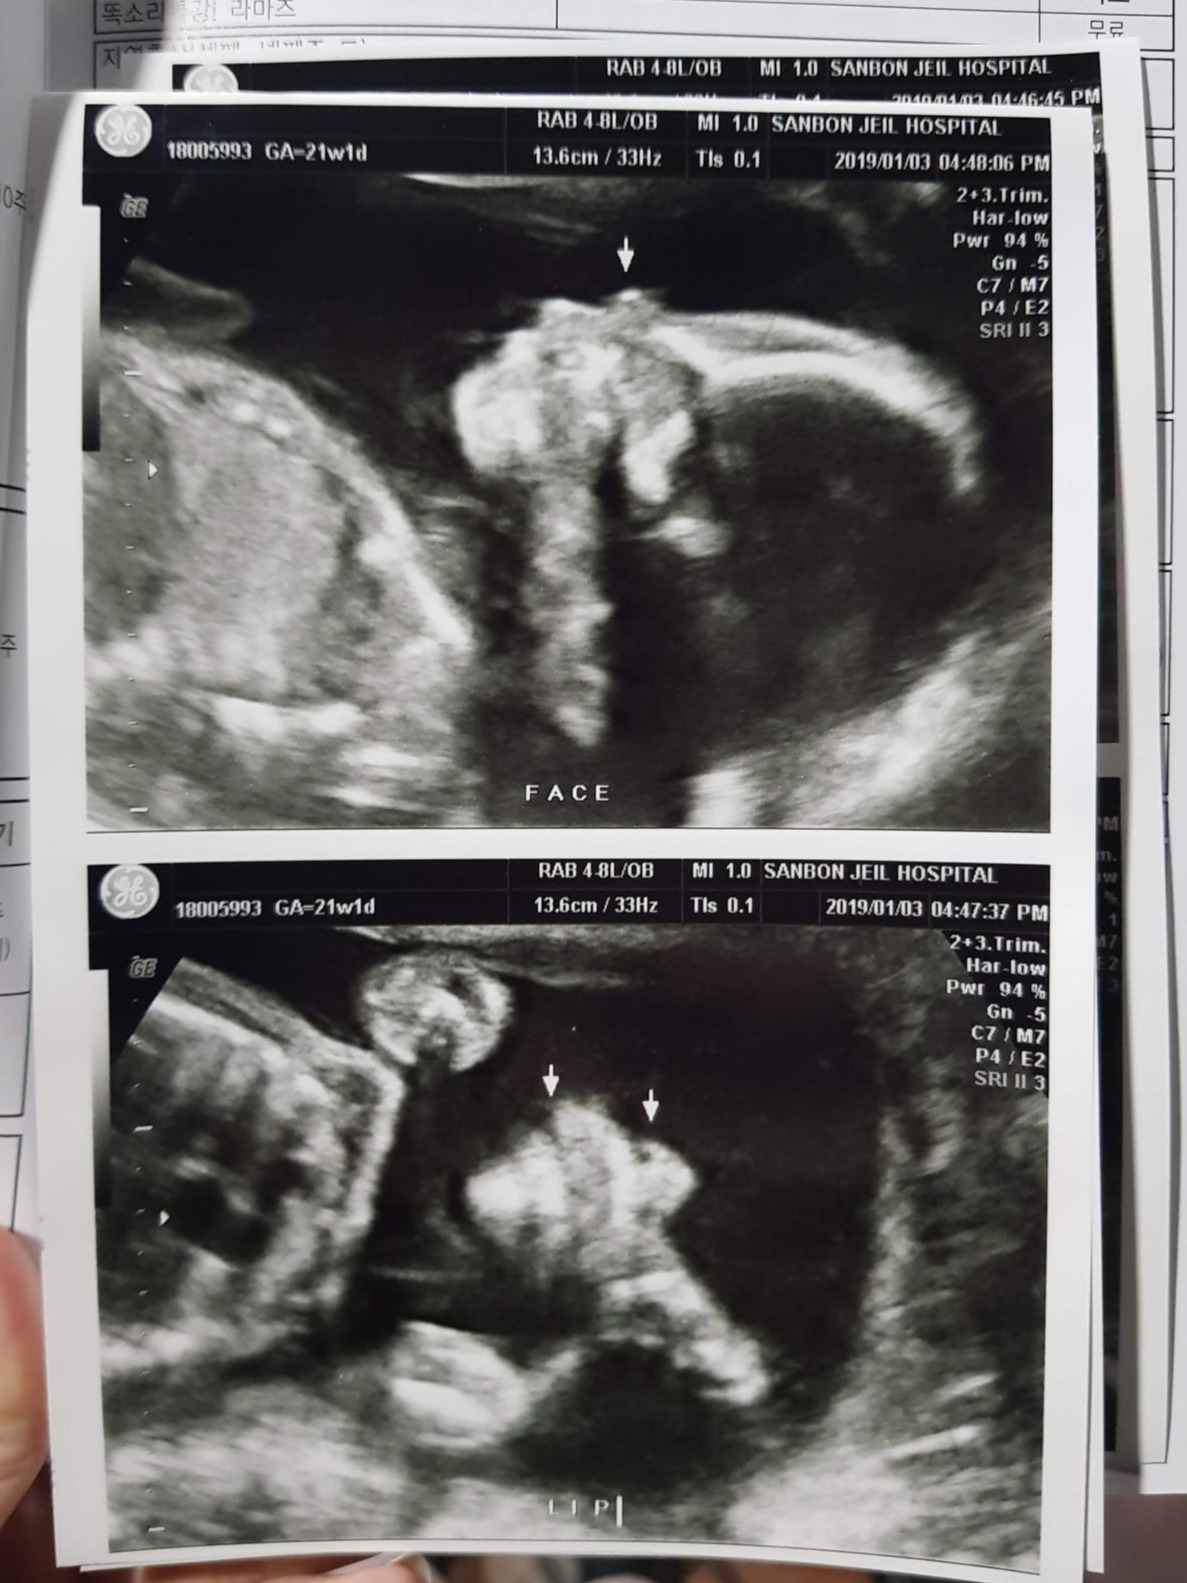

20190103_171801.jpg 건강한 우리 짠짠이! 잘생겼다!